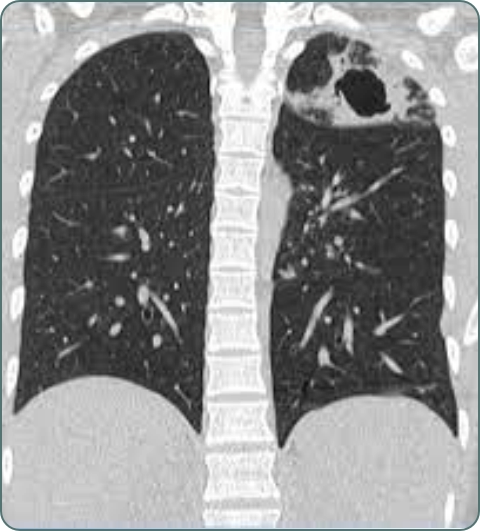

CT Scan Chest

Detailed cross-sectional imaging of chest for complex conditions. High-resolution CT for interstitial lung disease and lung cancer screening.

Lung Cancer

Cancer affecting lungs, often caused by smoking. Early detection is crucial for treatment success. Symptoms include persistent cough, chest pain, and weight loss.